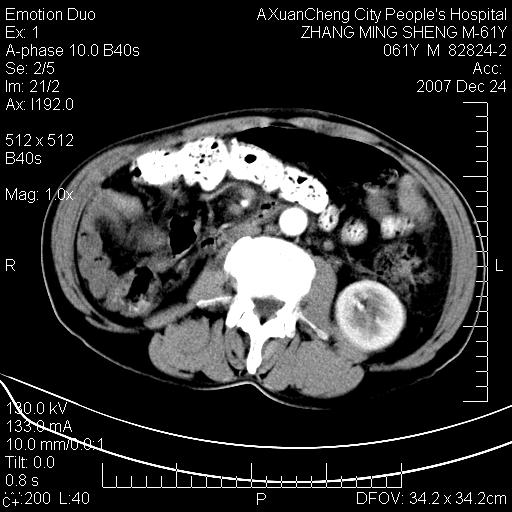

标题: CT11031:M61Y,胰腺占位 [打印本页]

标题: CT11031:M61Y,胰腺占位

大家侃侃门静脉和胆管系统怎么回事,肝内转移?

2,肝内多发结节状低密度占位,伴门脉及肠系膜上v栓子形成.考虑a;门脉及肠系膜上v血栓后肝改变.b;弥漫型肝癌伴门脉及肠系膜癌栓.

肝硬化,门脉高压,脾肿大;弥漫性肝癌,肝内、门脉、腹膜后淋巴结转移,肝内外胆管扩张,胰头区占位,建议mr检查

胰腺癌伴肝内转移;门脉、肠系膜上v癌栓形成。

考虑为:胰腺癌伴肝脏转移、腹膜后淋巴结转移,门静脉及肠系膜上静脉瘤栓形成。

胰体尾癌伴肝内转移,门静脉及肠系膜上静脉瘤栓形成.